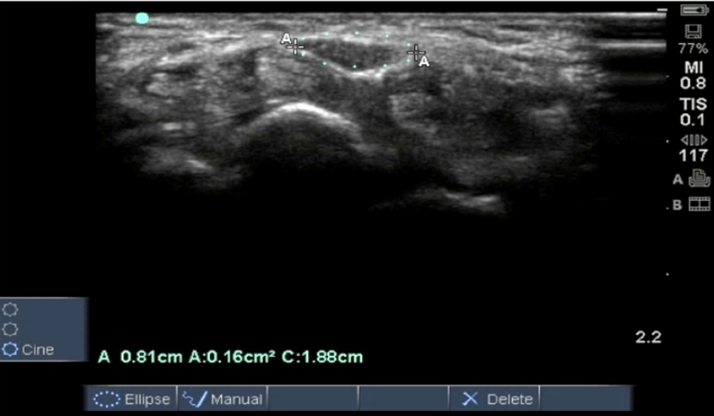

近年、手根管症候群の診断において、超音波(エコー)検査の有用性が非常に高まっています。エコー検査は、放射線被曝の心配がなく、リアルタイムで体の中を観察できる安全な検査です。手根管症候群の診断では、エコーを用いることで、圧迫されて腫れている正中神経を直接見ることができます。神経の断面積を計測し、正常範囲を超えていないかを確認することで、客観的な診断が可能になります。また、手根管内の腱の炎症や、ガングリオンなどの圧迫の原因となる他の病変がないかも同時に確認できます。

図:A/B=正中神経の深層(A)、浅層(B)に針があり、癒着を剥がしている

* MN: 正中神経、 * アスタリスク(\*): 注入物、TCL: 横手根靭帯、FCR: 橈側手根屈筋腱、FPL: 長母指屈筋腱、S: 浅指屈筋腱、 P: 深指屈筋腱、SCA: 舟状骨、CAP: 有頭骨)